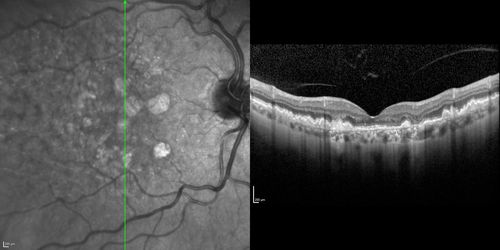

Dry AMD - Confluent Drusen Sparing Center of Macula which has Atrophy

65 year old woman, VA 20/40 OD; 20/80 OS. The center of the macula has few or no drusen with predominantly non-geographic atrophy